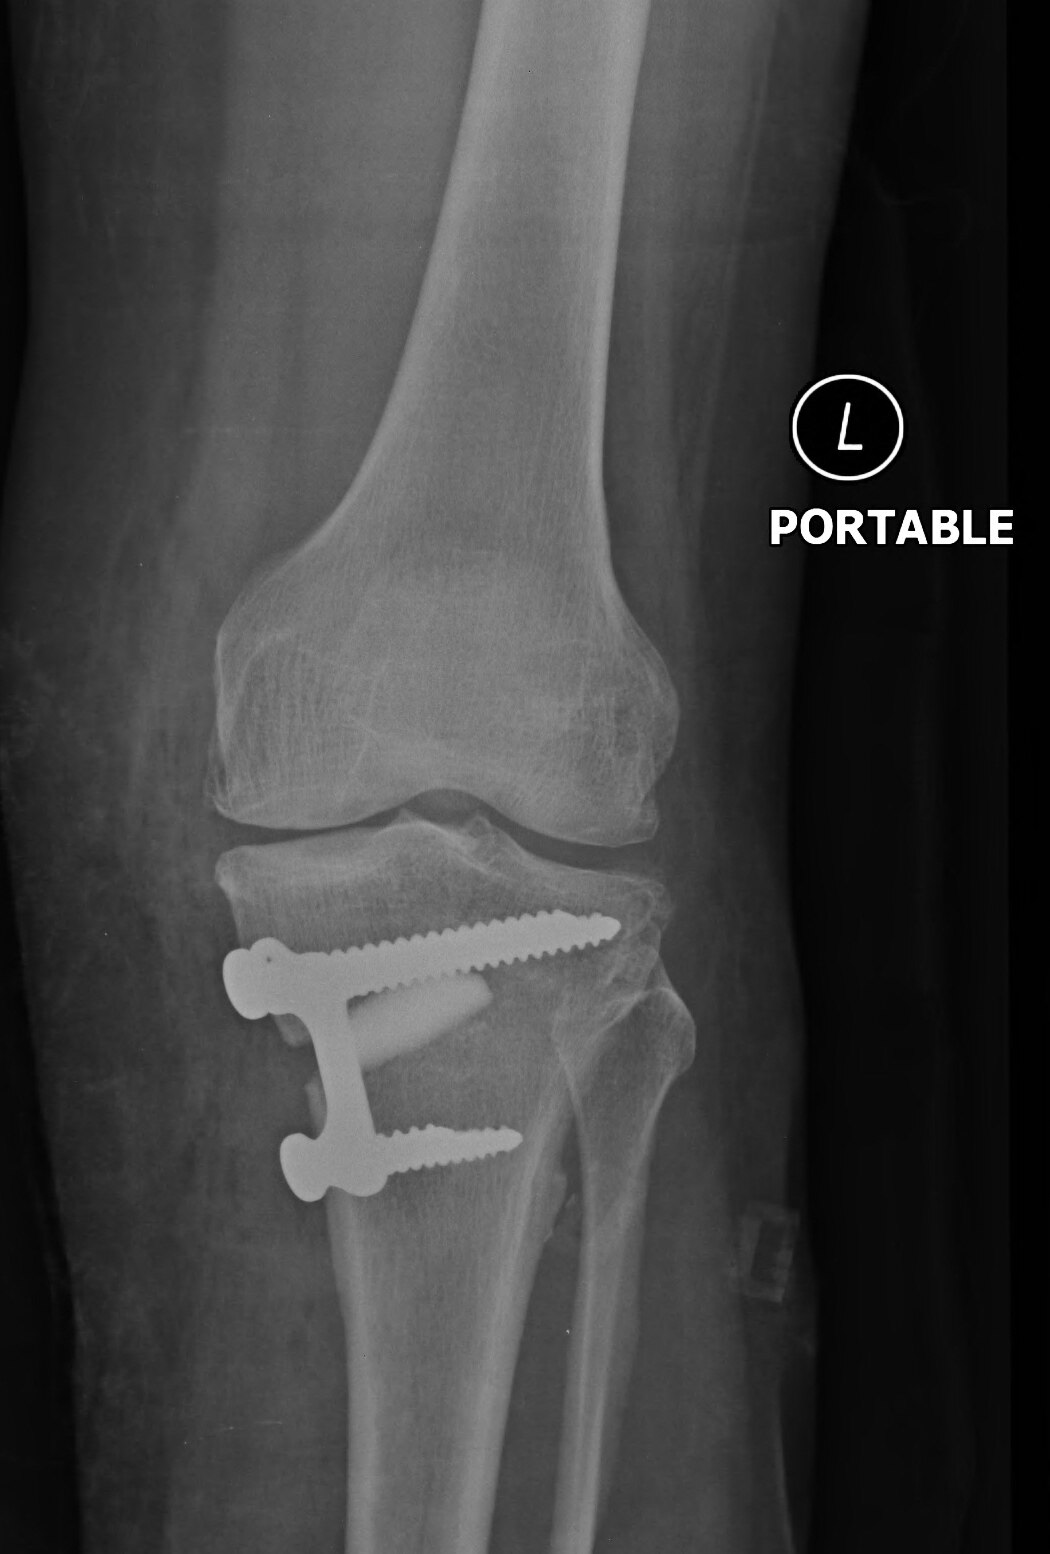

services